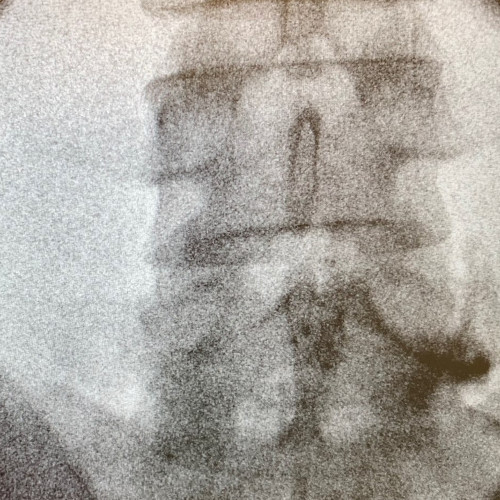

Röntgen-gezielte Infiltrationsbehandlung – Für eine Röntgen-gezielte Infiltrationsbehandlung ist ein stationärer Aufenthalt von einem Tag notwendig und wird von mir im Franziskusspital Margareten durchgeführt. Röntgengezielt sind auch Behandlungen mit Thermokoagulation und gepulster Radiofrequenz möglich.

- Röntgen-gezielte Infiltration der Facettengelenke

- Röntgen-gezielte Infiltration der Facettengelenke mit Thermokoagulation (Nervenverödung/Denervierung)

- Röntgen-gezielte Infiltration der Nervenwurzel

- Röntgen-gezielte Infiltration der Nervenwurzel mit gepulster Radiofrequenz